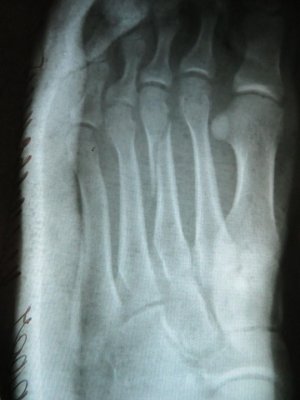

На следующий день повёз брата к целительнице, и заодно показал свою ногу. Она мне сказала, что там перелом. В травмпункте информация подтвердилась (сделали рентген который остался у врача). Оказалась сломана третья плюсневая кость, и мне просто наложили гипс прописали ОСТЕОГЕНОН (1т 2р/д).

Через неделю сделали повторный снимок, на котором я не заметил особых изменений, и наш травматолог для успокоения совести (по его словам) отправил меня на консультацию в больницу (решить вопрос о установки спицы).

Сегодняшний рентгеновский снимок прилагаю.